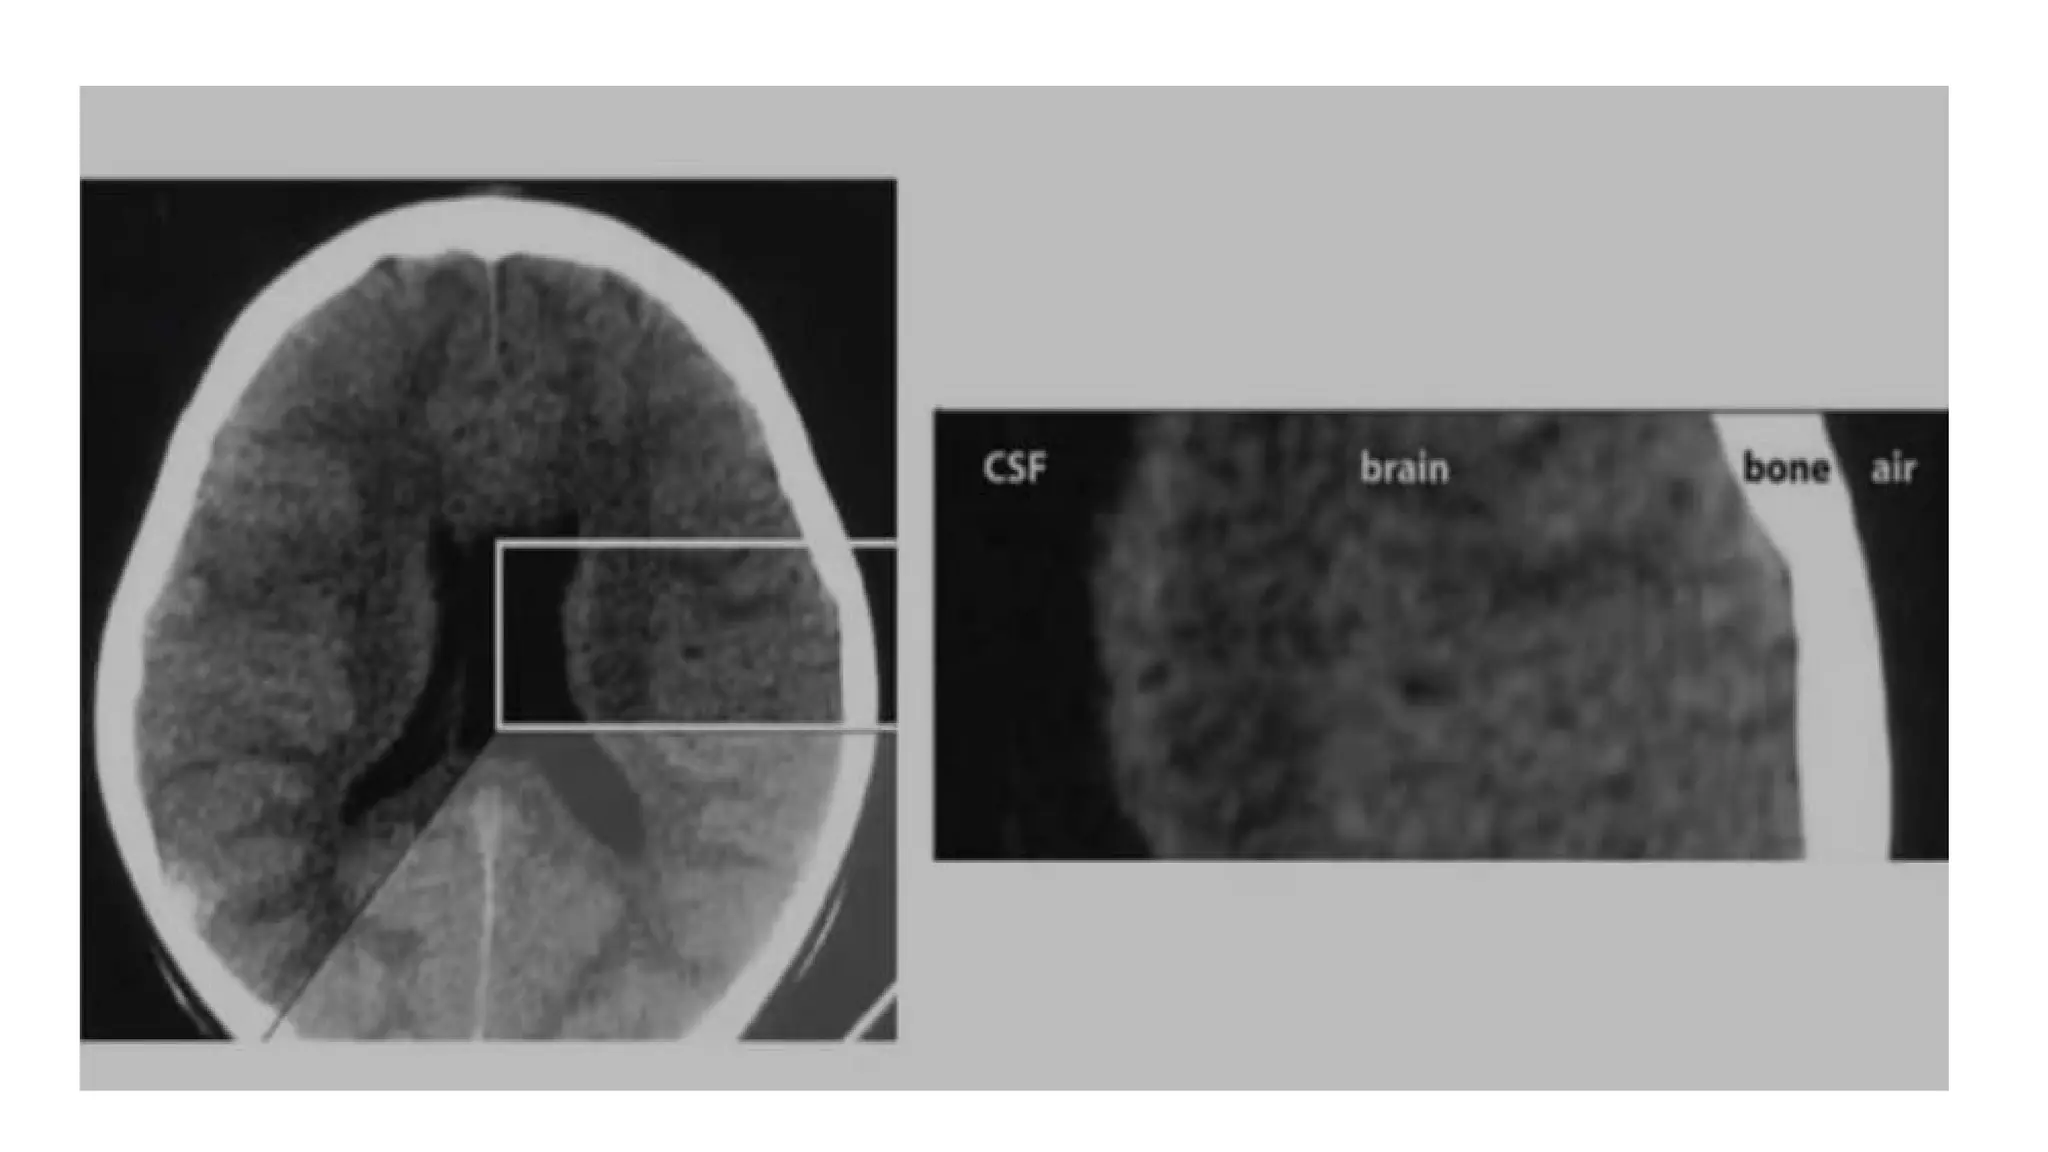

• Always describe CT findings as densities- isodense/hypodense/hyperdense.

• Higher the density = whiter the appearance

• Lower the density = darker the appearance

• Higher density than brain-hyperdense ( skull is the best example)

• Anything darker (lower density) than brain= hypodense( CSF and air are

classical examples)

X-RAYS ARE ABSORBEDTO DIFFERENT DEGREES BY DIFFERENT TISSUES • Always describe CT findings as densities- isodense/hypodense/hyperdense. • Higher the density = whiter the appearance • Lower the density = darker the appearance • Higher density than brain-hyperdense ( skull is the best example) • Anything darker (lower density) than brain= hypodense( CSF and air are classical examples)